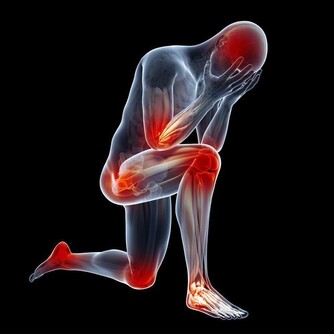

*****5、 肩頸痛*****

心髒病顧名思義是心臟出了問題,但是有人指出出現毫無徵兆的肩頸臂痛的話要小心心髒病。原來心臟缺血的時候會把疼痛的信號通過神經傳遞給在同一水平線上的脊髓段,而正好肩膀、脖子、下巴、手臂等器官就在這個區域內,所以說這些地方如果有痛感的話,就要小心是不是突發心髒病了。文章來源: https://wj.toutiao.com/q/125515/9R9jL421/6d22/#/